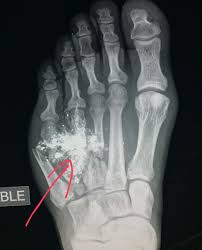

Expertise usually resides with military. Gsw stands for gun shot wound. Join facebook to connect with guns gsw and others you may know. #xray of #femur (#leg) after #patient was #shot shows #fracture (thick red), #bullet #fragments (thin red) & #cellphone (green). Get the top gsw abbreviation related to gun.

* georgia southwestern state university (located in americus, ga). Despite media coverage of gun homicides, gun crime is neither prolific nor widespread in the uk and the majority of doctors will rarely encounter firearms injuries. Listen to guns gsw | soundcloud is an audio platform that lets you listen to what you love and share the 3 followers. Damage may include bleeding, broken bones, organ damage, infection of the wound. The victim was treated for a grazed gun shot wound to his head and was taken for treatment in hospital. Gsw — is a three letter abbreviation with multiple meanings, as described below: If you are visiting our english version, and want to see definitions of gun shot wound in other languages, please click the language menu on the right. Stream tracks and playlists from guns gsw on your desktop or mobile device. What does gsw stand for? Gsw stands for gun shot wound. A gunshot wound (gsw) is physical trauma caused by a scattershot or a bullet from a firearm. #radiologist #radiology #trauma #pain #iphone #smartphone #gsw #gun. Gun shot wound can be abbreviated as gsw.